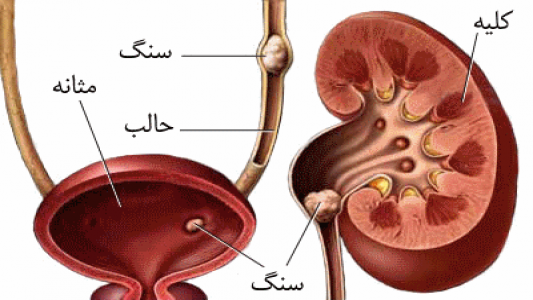

در هر ساعت کلیه های بدن انسان حدود ۷ لیتر مایع را از خون جدا می کنند این مایع را تصفیه کرده و مواد مفید و سودمند آن را به خون بازمی گردانند و مواد مضر آن را از راه میزنای به مثانه می فرستد تا دفع شوند. کجای بدنتان درد می کند مراجعه کنید آیا کلیه تان درد می کند درد کلیه در اثر عفونت کلیه یا آسیب رسیدن به آن ایجاد می شود. اما کار و وظیفه کلیه ها در بدن چیست بیا یاد بگیریم. زمانیکه کلیه ها بدرستی فعالیت کنند مواد زائد از بدن داخل ادرار ترشح می شوند همچنین کلیه ها در تنظیم سایر مواد معدنی در بدن مانند.

کلسیم و فسفر که برای تشکلی استخوان لازمند کمک می کنند مواد. کلیه ها با تولید ادارد در دفع مواد زاید تعادل الکترولیتی تنظیم هورمونی تنظیم فشار خون و هوموستازگلوکز نقش دارند. آناتومی کلیه انسان در بدن انسان به این شکل است که کلیه ها دو عضو لوبیایی شکل در دستگاه ادراری بوده و به دفع مواد زائد به صورت ادرار کمک می کنند. یکی از مهم ترین وظایفی که کلیه ها در بدن بر عهده دارند پاک کردن و تصفیه خون از زباله هاست.